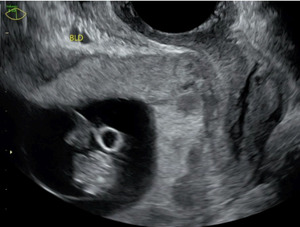

On admission for planned D&C, consents for laminaria placement, suction dilation and curettage under ultrasound guidance, possible uterine artery embolization, and possible hysterectomy were discussed and signed. The patient then underwent successful placement of a large and a medium-sized laminaria without complication. She subsequently underwent suction D&C with ultrasound guidance (Figure 3). Despite the prophylactic placement of 400 micrograms of rectal misoprostol and the administration of 20 units of Pitocin in IV fluids at the start of the case, the patient experienced significant hemorrhage during the procedure with an estimated blood loss of 1500 mL. Intraoperative findings raised concern for uterine rupture (Figure 4). A Foley balloon inflated with 30cc of saline was placed for attempted intrauterine tamponade (Figure 5), and a brisk blood loss of 500 mL immediately filled the foley catheter bag. Vaginal packing and intramuscular methergine were given as additional attempts to control the bleeding, but the patient’s hemodynamic status rapidly deteriorated. This necessitated volume resuscitation and transfusion of two units of packed red blood cells. An emergent exploratory laparotomy was then performed to identify the source of the bleeding with preparedness to repair any defects or perform a hysterectomy to prevent exsanguination. A thorough survey of the uterus, adnexa, and adjacent pelvic structures revealed no overt source of bleeding, uterine rupture, or organ invasion. The uterine and bladder serosa were intact. No hemoperitoneum was found. Further inspection revealed no additional blood loss beyond the 500 mL noted in the foley bag. Blood loss was ppropriately corrected for, and the patient became hemodynamically stable. The abdomen was closed, and the patient was transferred to interventional radiology for uterine artery embolization, prevented additional bloodloss. Following embolization, the patient was noted to be stable and extubated without issue.